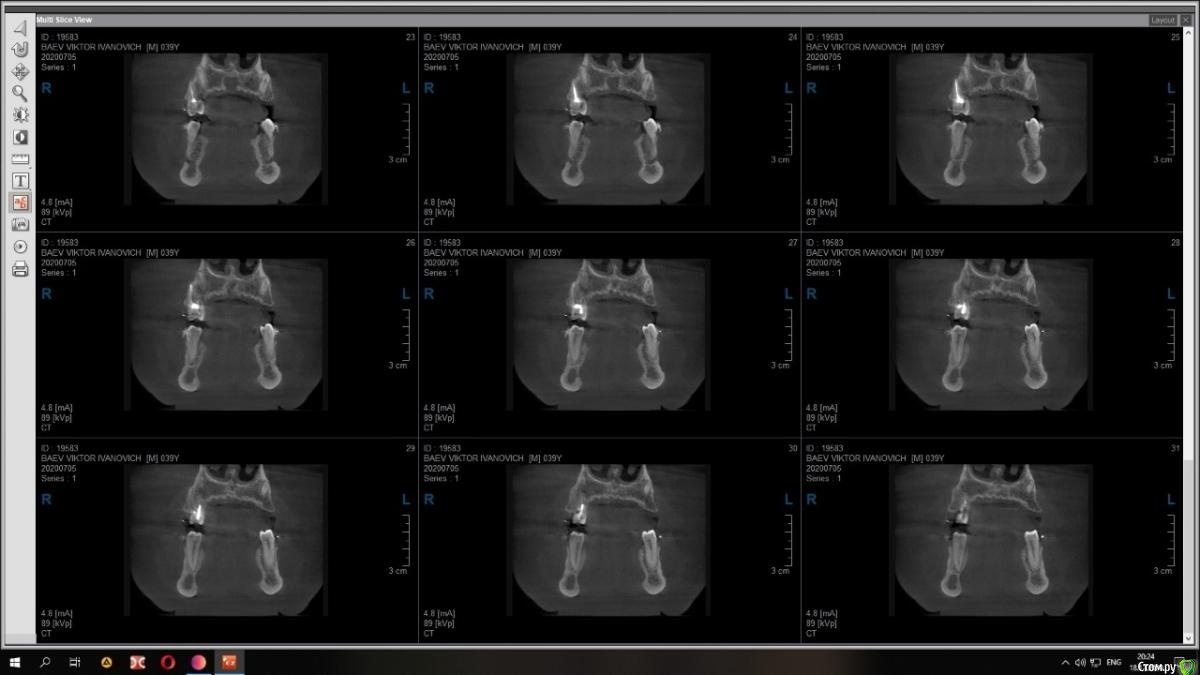

Raystom Опубликовано 15 декабря, 2020 Поделиться Опубликовано 15 декабря, 2020 Случайно на КТ перед имплантацией 36 обнаружили образование. Похоже на кисту резцового канала. Срезы снимка прилагаются.Варианты решения:1. Стационар и ЛОР, т.к. судя по снимку она, на мой взгляд, состоит из 2х частей и есть очень большая вероятность прорастания в носовой ход2. Убирать самостоятельно, но тут возникает очень много вопросов. С нёба доступ самый простой, но потом непонятно как закрыть костный дефект так, чтобы была возможность восстановления кости. При вестибулярном доступе предварительно придется делать эндо 111 с последующей резекцией, но, непонятно, удастся ли его вообще сохранить. Ещё момент, если убрать только обширную часть (нижний компонент), положить резорбируемую мембрану на дно, а аугментат через 2 месяца, дабы не пророс. При этом верхний компонент убрать с помощью ЛОР-эндоскопии.И организационный вопрос, как будет лучше, как и планировалось провести имплантацию 36, дать человеку отдохнуть на новогодних праздниках, а после уже лечение по поводу кисты Ссылка на комментарий

Raystom Опубликовано 18 декабря, 2020 Автор Поделиться Опубликовано 18 декабря, 2020 Срезы из других проекций Ссылка на комментарий

Raystom Опубликовано 21 декабря, 2020 Автор Поделиться Опубликовано 21 декабря, 2020 Киста то малюсенькая. Вскрыть и почистить. Нёбно конечно же. Можно положить мембрану, в полость ничего не класть. В нос я бы вообще пока не лез. меня смущает 3 момента, первый это то, что она прилетит рядом с апикальной частью 11, второй это то, что мне показалось она состоит из 2х частей и третье, это то, что она около 1см в диаметре (просто пока она не выросла и натворила дел, с ней можно что-то сделать) плюс ко всему стоят брекеты и мне кажется это может ускорить процесс роста кисты Ссылка на комментарий